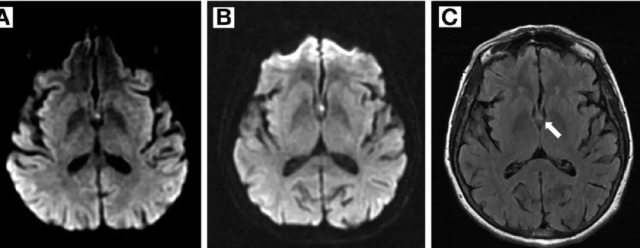

为了更好的了解病情,医生建议李女士做个头颅MRI检查,没想到还真的把原因给揪出来了--急性梗死灶。

到这里,病情就很清楚了,因为脑内发生了梗死灶,这个梗死灶阻断了海马体的血液供应,导致短暂性全面遗忘的出现。这次“乌龙”就诊,不仅解决了“乌龙”事件,还把隐藏的危险疾病揪出来,真是“塞翁失马,焉知非福啊”!